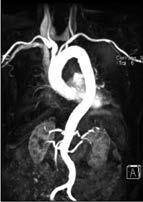

MR-Angiographie: Die MRA der Aorta bietet eine hervorragende Übersicht (Abb. 5a) und ist hier der FKDS überlegen. Die fehlende ionisierende Strahlung macht die Methode attraktiv auch gegenüber der CTA.

Abb. 5a Abb. 5b

Abbildung 5a, b: Darstellung der Aorta.

a: Mit MR-Angiographie erhobene Übersicht.

b: CTA-Darstellung einer langstreckigen Aortendissektion Typ A.